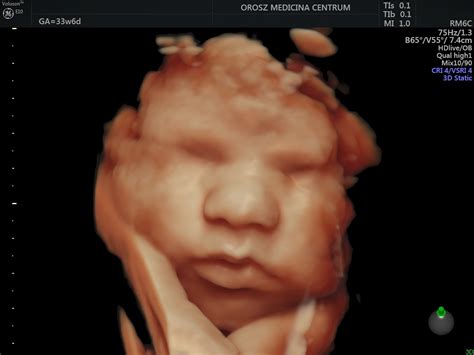

3D/4D/5D Ultrahang (Babamozi)

A 3D, 4D és 5D ultrahangok elsődleges célja nem a fejlődési rendellenességek megtalálása, hanem a magzat külalakjának megmutatása a szülőknek. A 3D a méhen belüli magzatról egy fotórealisztikus állóképet készít. A 4D a negyedik dimenzió, az idő, ami egy fotórealisztikus videófelvételt jelent. Az 5D az új generációs, gyors 3D-s technikák segítségével könnyebben lehet a felszíni és a mélységben lévő struktúrákat megtekinteni. A gép önállóan tud nyaki redőt, szívet, gerincet, agyat vagy petefészek tüszőket vizsgálni, mérni. A 3D és mozgó képeknél is újabb, realisztikusabb a képalkotása. Beállítható, hogy „honnan süssön a Nap”, milyen tónusa legyen, milyen mélységbe lásson le a készülék. Legalkalmasabb a 20-32. terhességi hét közötti időszak, különösen a 24-30. terhességi hét.